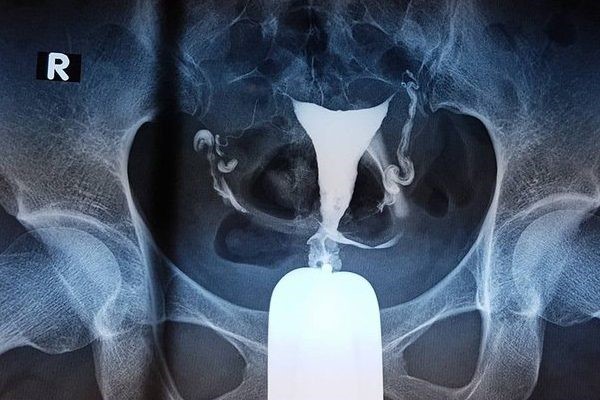

Để có thể thực hiện được phương pháp này, bạn cần được sử dụng cách chụp bằng X-quang sau khi đã thực hiện bơm thuốc cản quang áp lực thấp vào các bộ phận của tử cung như: cổ tử cung, buồng tử cung,…

Sau đó, bạn sẽ được các bác sĩ đặt dụng cụ vào âm đạo, lau cổ tử cung bằng dung dịch sát khuẩn đồng thời đặt ống thông vào trong lỗ cổ tử cung. Và sau đó bạn sẽ được bơm chất cản quang bào trong cổ tử cung qua ống thông đã được đặt ở phía trên.

Nếu vòi trứng của bạn thông suốt, dung dịch quản quang sẽ đến phần hai vòi trứng cùng với ổ bụng. Sau đó, chất cản quang sẽ được hấp thụ một cách tự nhiên tại ổ bụng. Tuy nhiên nếu như phần vòi trứng của bạn bị tắc thì dung dịch cản quang sẽ không thể đi qua được.

Trong quá trình thực hiện chụp vòi trứng tử cung, bạn sẽ được chụp ở nhiều tư thế để có thể quan sát được toàn diện và rõ nhất. Sau khi đã có kết quả, bác sĩ sẽ rút ống thông và mỏ vịt ra khỏi cơ thể bạn.